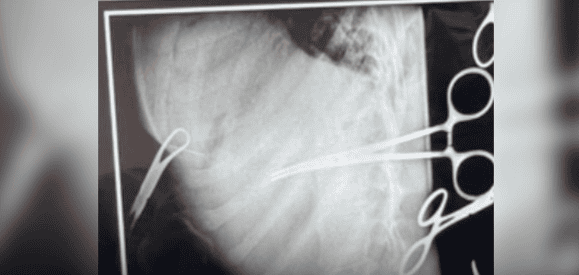

Gjilpërën që e pati në dorë e ktheu kah vetja. Me të 14 vjeçarja E.H nga Klina dyshohet se u vetëshpua në mes të gjoksit. Gjilpëra më pas i depërtoi brenda organeve vitale.

Ekzaminimet filluan menjeherë, nga të cilat u vrejt gjilpëra brenda trupit të saj.

Pas konsultave mes mjekëve, mëngjesin e 4 shkurtit, kirurgët torakal në bashkëpunim me ata të fëmijëve e anesteziologët, kryen intervenimin që zgjati jo pak.